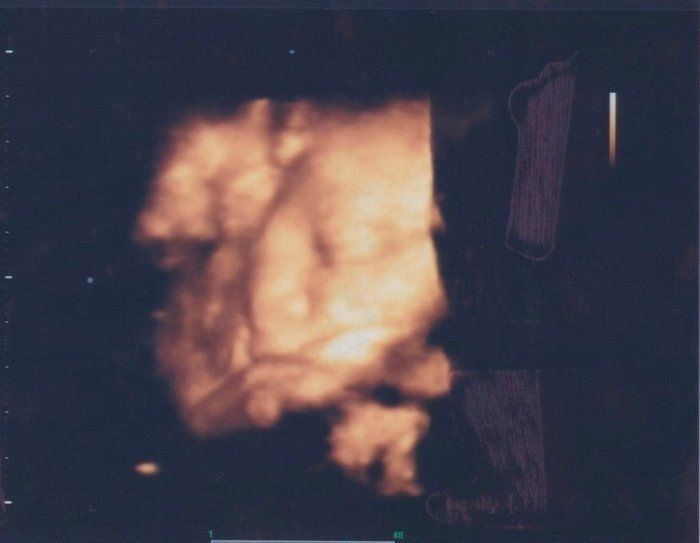

なつさんの妊娠35週目のエコー写真 顔立ちがよりはっきりとしてきました

もう生まれてきても良い週数が近づき、最後の検診でした。顔立ちもよりはっきりしてきて、どちらに似ているかと考えたりもしました。顔を見ると早く会いたいなと、生まれてくるのが楽しみになりました。さらにこの頃は真夏だったので、暑くてお腹はいよいよパンパン。動くのも大変で苦しかったので、早めに出て来てくれないかなとも思っていた時期でした。